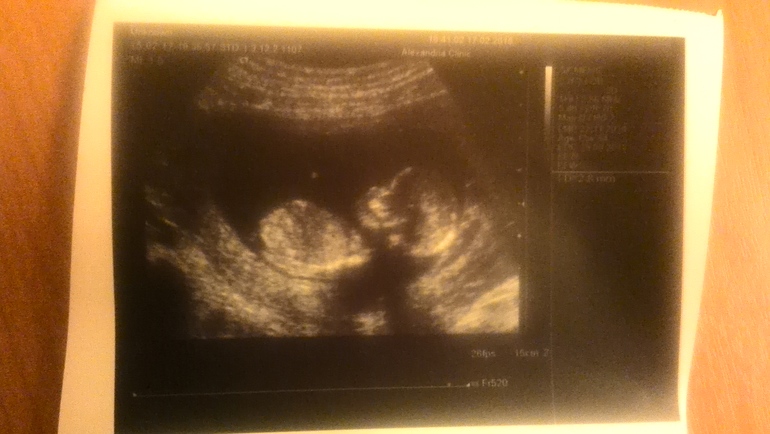

наш перввый скрининг, узи )

Вчера сделали первый скрининг, кровь пока не готова, завтра рез-ты будут.

По узи все нормально, рук две, ног две, голова и нос. И все это очень дрыгастое.

Пдр 29 августа

Ктр 64мм

Бпр 22мм

Ог 79мм

Ож 63 мм

Дб 9мм

Сб 162 уд/мин

Твп 1.9

Нос 2.8мм (опять носатый походу, в папу)

Кровоток норма, ПИ 1.01

Локализация хориона-передняя.

Пол неясен, ну и фиг с ним.

Срок 12-13 недель, по мес 12+3

Ну и фотка нашего головастика.